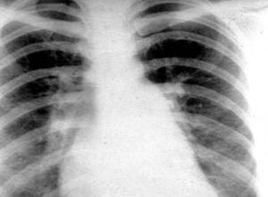

1、X線檢查對於臨床診斷十分重要,且可用以觀察肺水腫的分布區域。間質性肺水腫的特徵性表現為肺紋理增多變粗,模糊不清,肺野透光度低而模糊,肺小葉間隔增寬,形成KER-leyB線。肺泡水腫主要表現為腺泡狀增密陰影,相互融合呈不規則片狀模糊陰影,瀰漫分布油肺門兩側向外伸展,逐漸變淡,形成典型的蝴蝶狀陰影。有時兩肺中下野出現不對稱的大片陰影,與炎症不易區別。